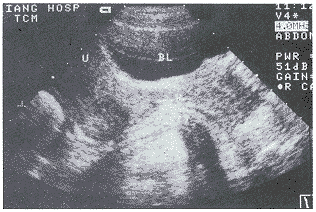

RC的超声诊断标准和分度的探讨:我们观察测量50例正常男女性仰卧位直肠声像图表现:在直肠肛管交界处前方可有1~10mm深的前突(图2),因此我们将≥10mm者列入异常统计。在临床治疗中,为了明确病变的严重程度,我们进行了分度的探讨。在观察中,我们发现症状严重者突出深度越深,而长度变短或变化不大,因此考虑以深度作为分度代表其严重程度。即前突深度10~20mm为轻度,21~30mm为中度,≥31mm为重度。本组轻度8例,中度13例(图3),重度3例(图4)。这种以深度为准的分度方法经临床观察、治疗是可行的。一般轻度者可采用中药治疗,中度以上可手术治疗,该分度法我们将在今后的工作中进一步研究探讨其可行性。

V:阴道,BL:膀胱,U:子宫

图3 中度RC(箭头所指)